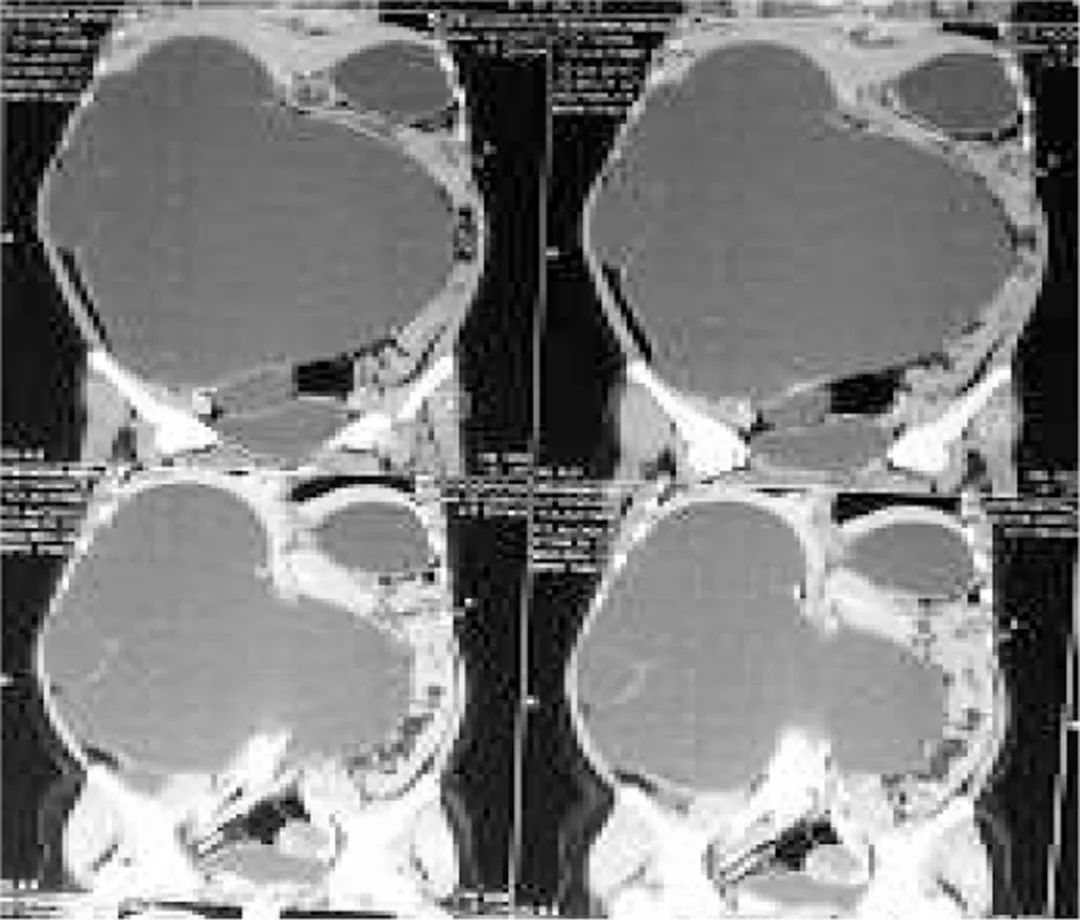

超声检查发现一个巨大的囊肿占据整个腹腔。腹部增强CT扫描显示腹膜后巨大囊肿占据整个右腹膜后腔,并跨越中线向左延伸(图2)。腹腔内其他脏器被推挤到腹部左侧。左肾清晰可见,不过在右腹膜后腔未见肾实质。初步诊断患者为巨大右肾积水。

图2 巨大腹膜后囊肿(右肾积水)占据整个右腹膜后腔,并跨越中线向左延伸